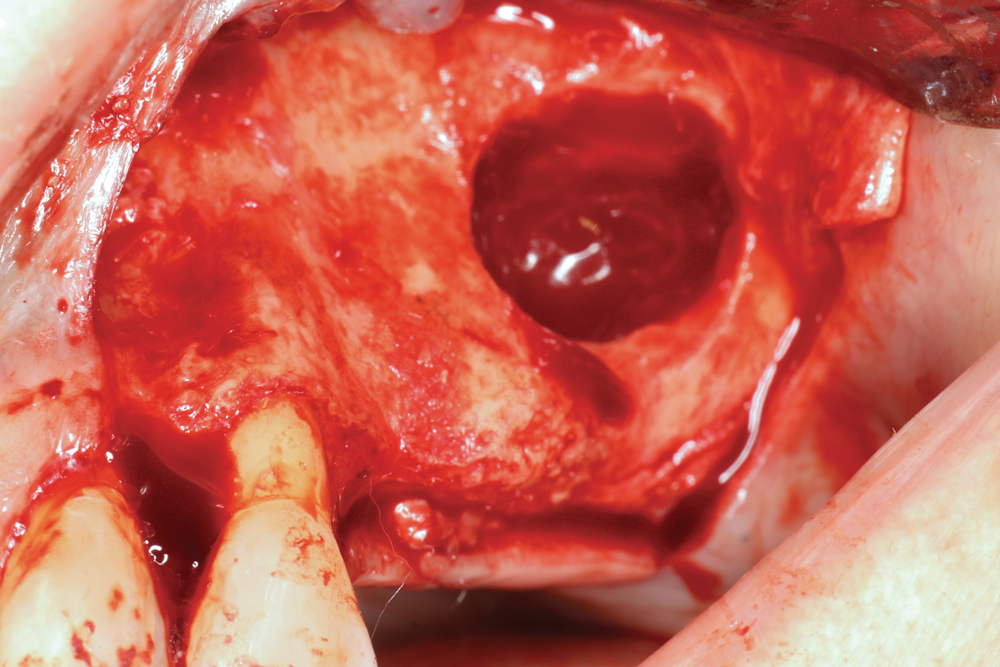

Fig 10. Intraosseous penetrations prior to graft placement at maxillary left quadrant lateral ridge augmentation.

Figure 10